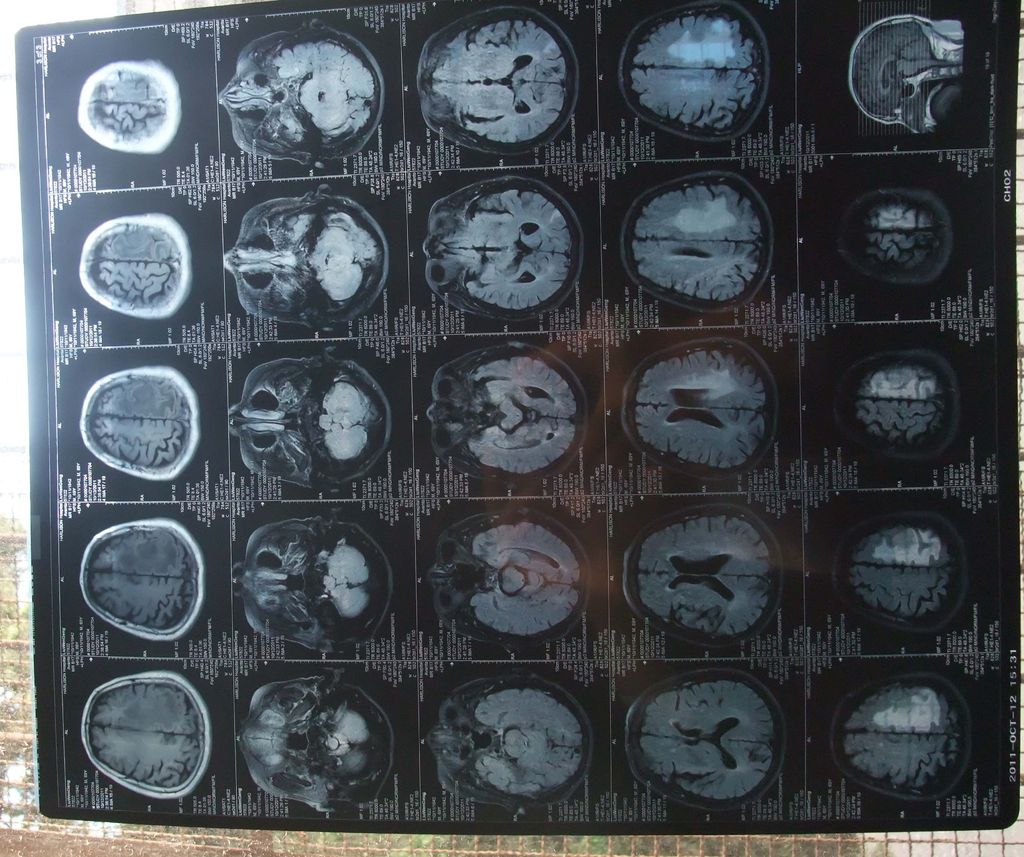

研究生医学影像学-颅脑2-中枢神经系统

图片尺寸1080x810